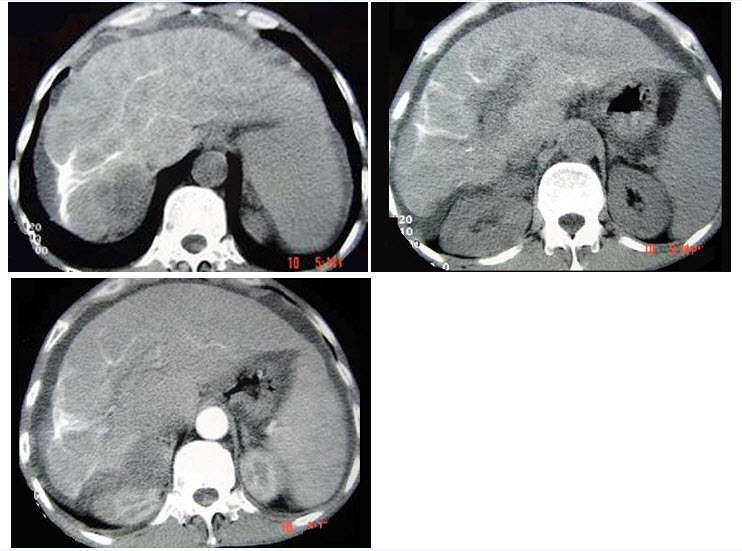

21、单项选择题

9个月女婴,头颅迅速增大,四肢肌力下降,CT表现如图,最可能的诊断是()

A.胼胝体发育不全

B.Dandy-Walker综合征

C.前脑无裂畸形

D.脑灰质异位

E.无脑回畸形